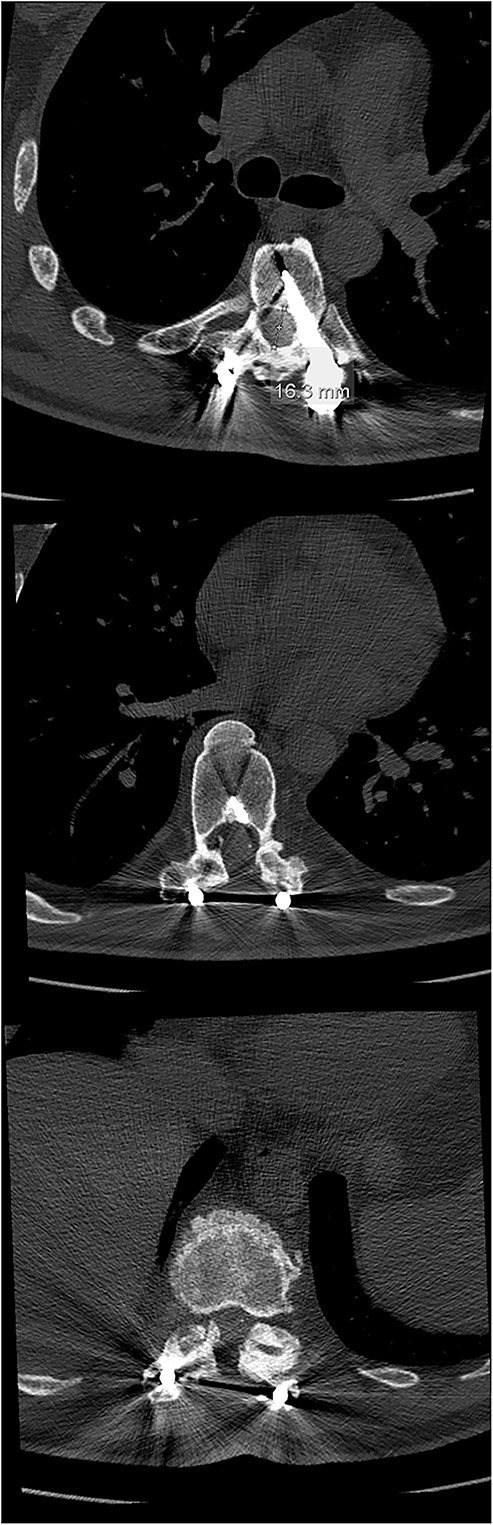

The initial CT scan (axial views), showing the width of the spinal canal at Th6 (above), Th9 (middle) and Th11 (below).

Final follow-up CT scan (axial views), showing adequate width of the spinal canal at Th6 (above), Th9 (middle) and Th11 (below).

The imaging studies revealed thoracic kyphoscoliosis (with a kyphotic curve of 50°, left upper-thoracic curve of 40° and right lower-thoracic curve of 25°) and significant stenosis of the thoracic part of the spinal canal (particularly at levels Th6, Th9 and Th11) due to severely ankylosed ligamentum flavum (OLF) and the concomitant degeneration of the facets (Figs 1 and 2). Imaging indicated thoracic myelopathy (Fig. 3). We performed emergent posterior wide laminectomy using an ultrasound bone scalpel, and a partial correction of the deformity by instrumented spinal fusion (Th6-Th12). The surgery was performed by the senior author (N.H.).

Computed tomography (CT) is considered the most useful diagnostic imaging modality in identifying the ossification of the spinal ligaments, including the OLF [3, 8]. In severe cases, the ossification can also include the dorsal area of the dura, making the surgical treatment of the OLF very challenging, with a high risk of a dural compromise and leakage of the cerebrospinal fluid [2, 5, 8, 10]. However, this was not the case with our patient.